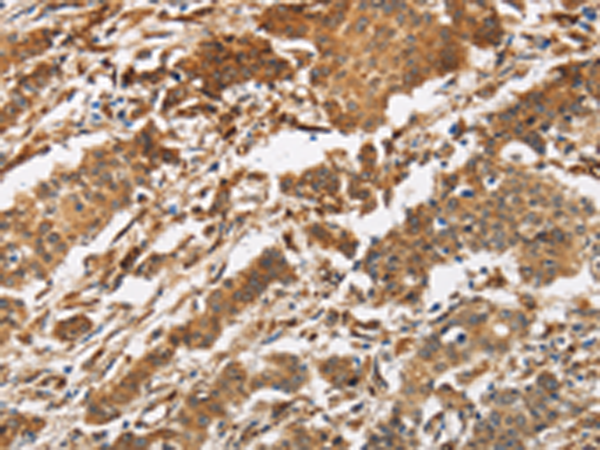

分类: 科研抗体货号: P01149别名:应用: IHC反应种属: Human, Mouse, Rat